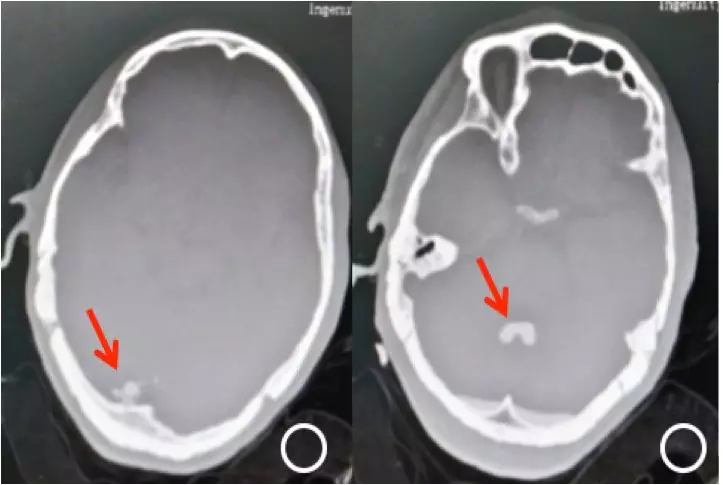

入院完善检查后,局麻下行“左眼脱位晶状体超声粉碎+后段玻璃体切割+眼内探查+重水+眼内光凝+气液交换术”。术中切除脱位晶状体周围玻璃体,超声粉碎吸除脱位晶体,切除所有玻璃体和积血,见颞下方及颞上方视网膜裂孔,视网膜隆起高,注入重水4ml,视网膜平伏。再行视网膜裂孔激光光凝,气压35mmHg气液交换,置换重水。准备缝合巩膜和结膜切口时,患者突发胸闷不适,随即呼之不应,血氧饱和度低,血压下降,考虑休克、呼吸衰竭。立即心肺复苏抢救,气管插管和机械通气,查肺动脉CT(CTPA):双侧胸腔积液伴肺膨胀不全,未见肺动脉栓塞;头颅CT提示:颅内积气,左侧眼球、小脑幕、第三脑室、中脑导水管及第四脑室内多发高密度影。结合患者病史和影像学资料,诊断为“眼内重水迁移入脑室”(图1)。立即转入ICU予以对症生命支持,同时行体外膜肺氧合术(ECOM)。ECOM持续4天后,患者神志转清。

图1. ①头颅CT平扫显示枕叶蛛网膜下腔高密度影,提示重水沉积于枕叶蛛网膜下腔;②显示重水蓄积于第四脑室。